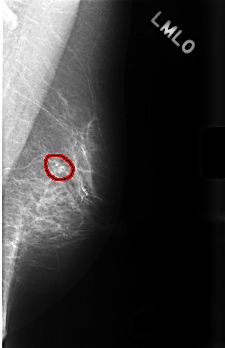

Digital Database for Screening Mammography

Volume: benign_14 Case: C-0476-1

C_0476_1.LEFT_MLO

LEFT_MLO LINES 4520 PIXELS_PER_LINE 2920 BITS_PER_PIXEL 12 RESOLUTION 50 OVERLAY

FILE: C_0476_1.LEFT_MLO.OVERLAY

TOTAL_ABNORMALITIES 1

ABNORMALITY 1

LESION_TYPE CALCIFICATION TYPE PLEOMORPHIC DISTRIBUTION CLUSTERED

ASSESSMENT 4

SUBTLETY 5

PATHOLOGY BENIGN

TOTAL_OUTLINES 1

BOUNDARY